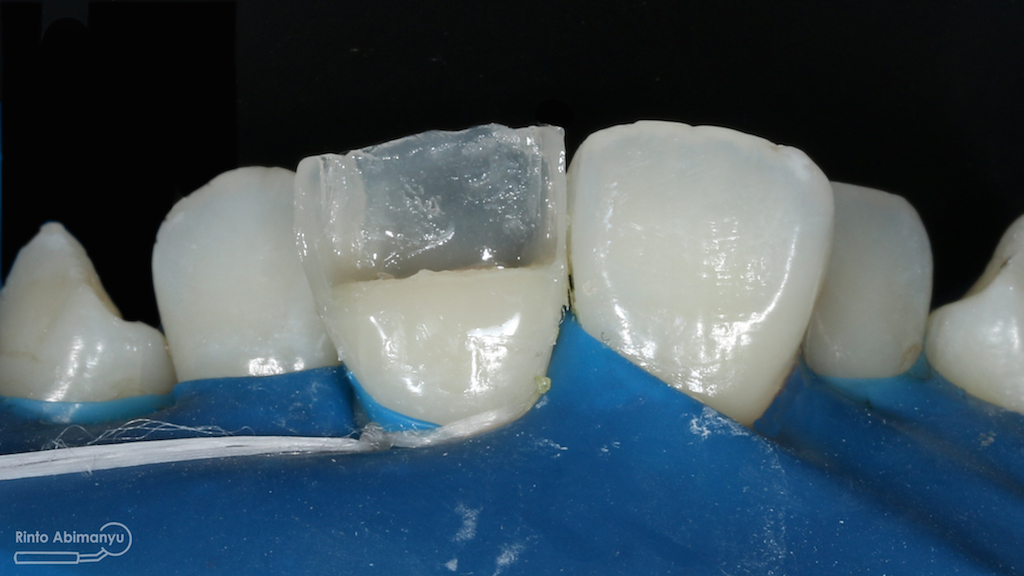

Untuk kunjungan pertama ini saya rencanakan melakukan perawatan saluran akar langsung pada dua gigi central… Saya pasang rubber dam untuk mengisolasi daerah kerja

Gigi 11 21 setelah dipasang rubber dam